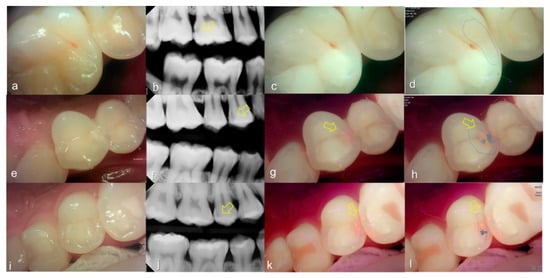

3.3. Crack

The values of the QLF parameter according to the value classified based on the QLF criteria were significantly different (Table 2). The cut-off value of |ΔFmax| and ΔRmax for determining a crack (QLF criteria scores 0 and 1 vs. 2) was 20.80 and 39.00, respectively. In addition, the AUROC of QLF parameters were similar (0.83, 0.82) (Table 3). Representative images of QLF and bitewing radiograph of dental cracks are shown in Figure 9 and Figure 10.

Figure 9.

Cracks: (a) white-light image of QLF, visual examination score 0 (No detectable crack line) on #15; (b) fluorescence image of QLF, QLF caries score 1 (fluorescence loss and red fluorescence present as a line in a crack site) on #15.

Figure 10.

Cracks: (a–d) QLF caries score 2 (fluorescence loss and red fluorescence glow extending around crack site) and visual examination score 0 (no detectable crack line) on #25; (e–h) QLF caries score 2 (fluorescence loss and red fluorescence glow extending around a crack site) and visual examination score 1 (ambiguous detectable crack line) on #17 (arrow 1), QLF caries score 1 (fluorescence loss and red fluorescence present as a line in the crack site) and visual examination score 0 (no detectable crack line) on #17 (arrow 2); (i–l) QLF caries score 2 (fluorescence loss and red fluorescence glow extending around a crack site) and visual examination score 2 (distinct detectable crack line) on #47; (a,e,i): white-light image of QLF; (b,f,j): fluorescence image of QLF; (c,g,k): bitewing radiograph; (d,h,l): analyzed QLF image using QA2 software.